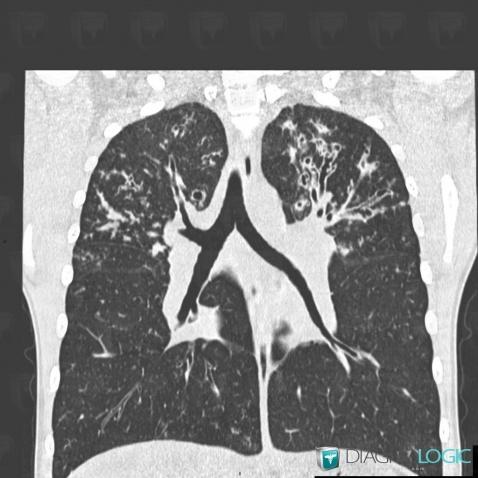

Mucoviscidose, Parenchyme pulmonaire, Scanner

Voici les informations spécifiques à l'image clé ci dessus:

- Diagnostic Mucoviscidose (lié à Impaction mucoïde), Localisation(s) Parenchyme pulmonaire, comportant les gammes Nodules pulmonaires multiples

- Diagnostic Mucoviscidose (lié à Bronchiolite ), Localisation(s) Parenchyme pulmonaire, comportant les gammes Micronodules centrolobulaires pulmonaires